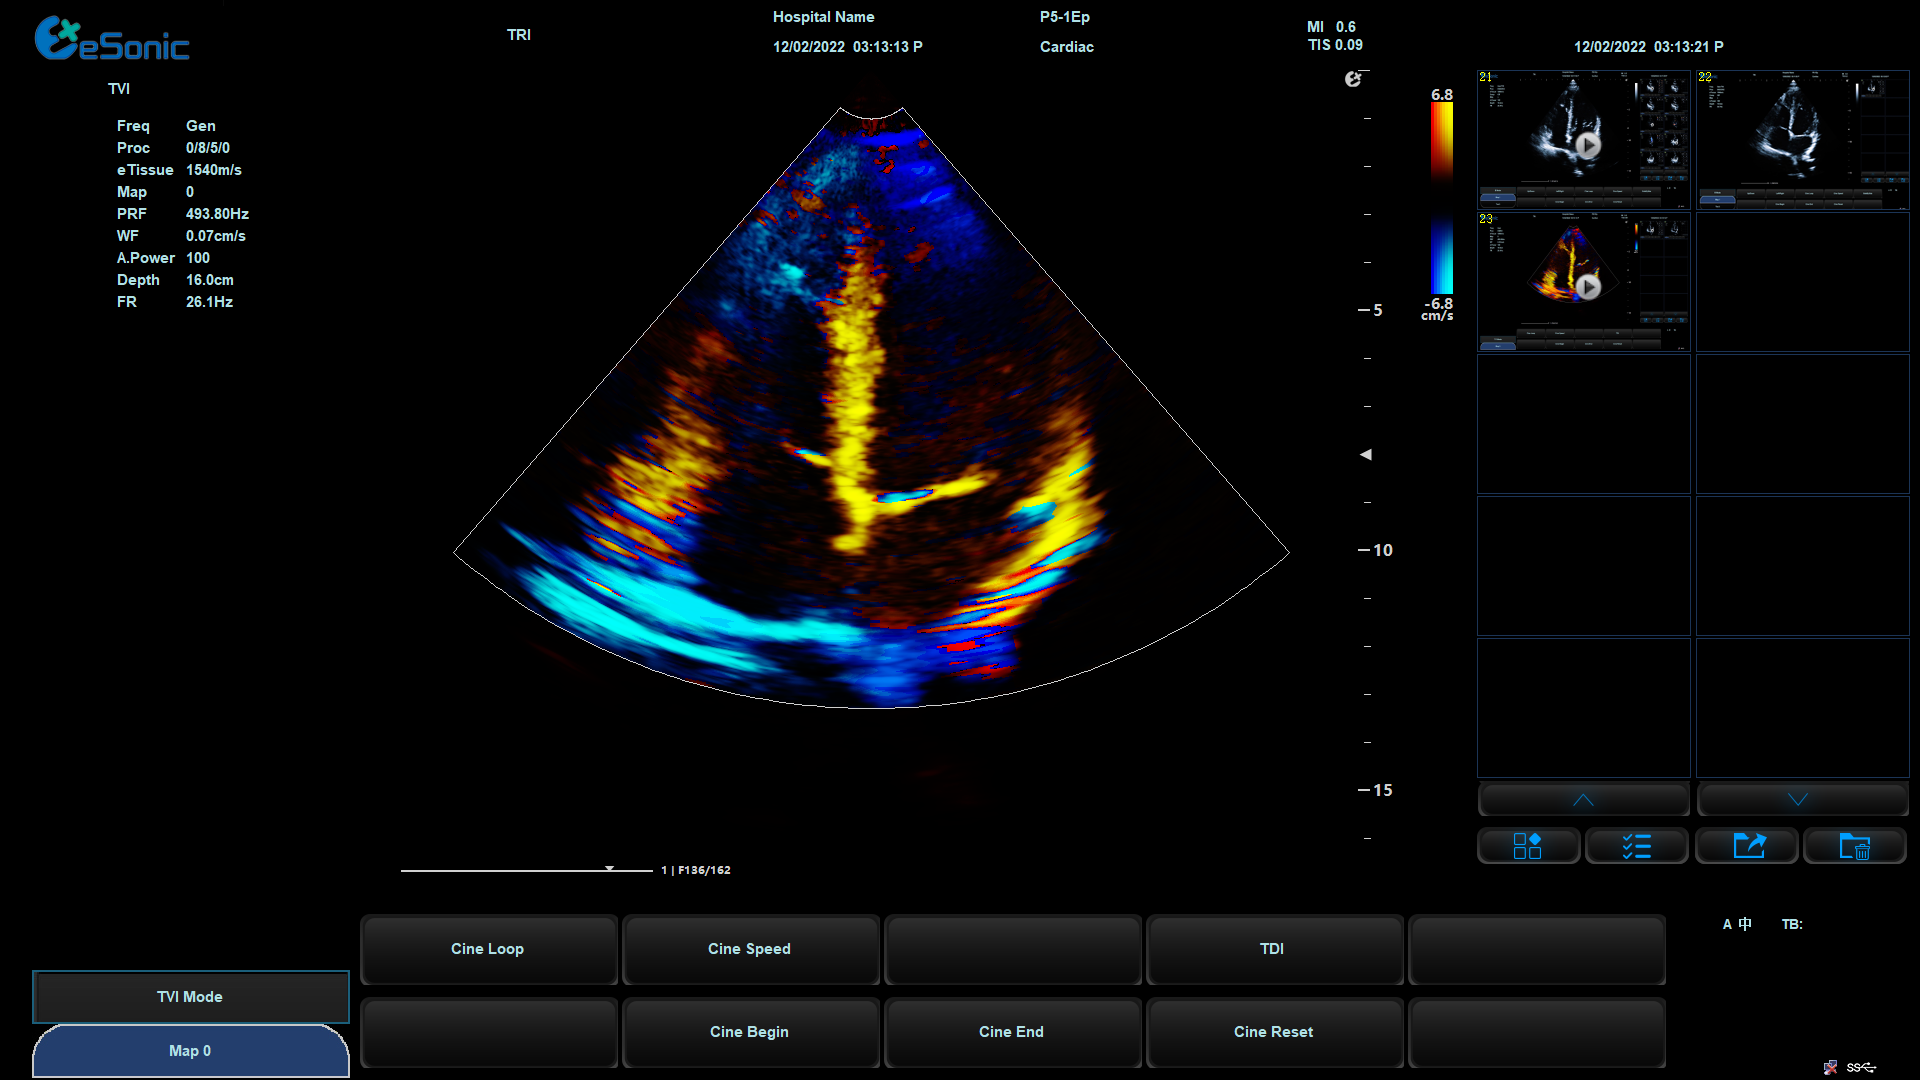

eHertz优异的TDI表现- 图像非常干净

组织多普勒

包含多种模式

可对室壁运动进行速度、加速度的测量和分析

观察心肌运动、定量分析心肌的运动速度变化,检测心肌供血情况

评价早期的舒张功能